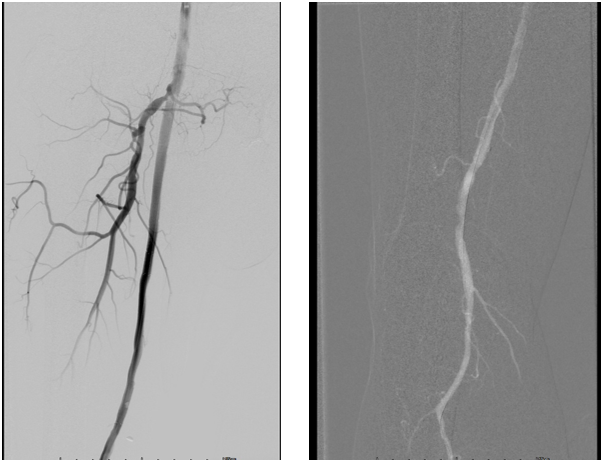

术前造影

手术过程

术中应用导丝配合4×220mm、5×220mm SABER球囊(10atm,3min)逐级扩张股浅动脉,顺利开通闭塞段,置入5.5×300mm DCB贴附,造影显示局部夹层,遂植入6×150mm SmartFlex和6×100mm SmartControl支架;

SABER球囊逐级扩张

DCB贴附

支架植入

支架植入后造影显示血流明显改善,流速可;

架植入后造影